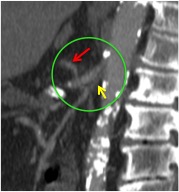

Flecha roja: colateral que repermeabiliza la AMS.